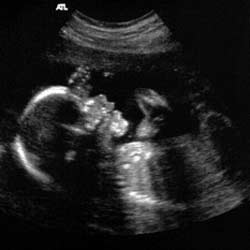

So why do so many people believe a sonographer when they say that their unborn baby weighs xlbs in utero? It’s the same sort of equation. An ultrasound gives the sonographer a view of a small section of the uterus at any one time and gradually builds up a picture as the transducer is moved across the abdomen. Three measurements are taken during a growth scan, the biparietal diameter (distance between the 2 sides of the head), femur length and the abdominal circumference. These measurements are entered into a computer program which then calculates the estimated weight based on charts created by researchers. You would think it would be fairly accurate. All that science.